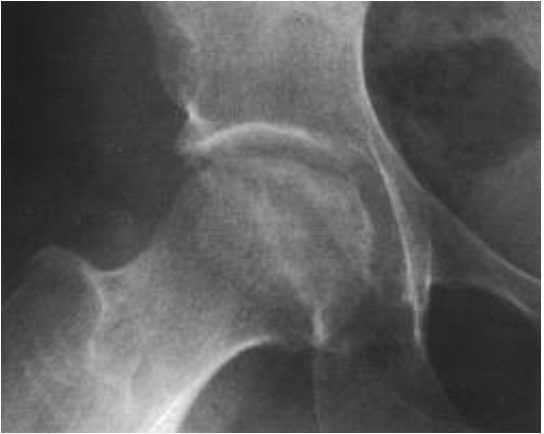

В ортопедии и травматологии рентгенологическое исследование используют для диагностики деформирующего коксартроза, артритов, асептического некроза головки бедренной кости, костных новообразований, вывихов, переломов шейки бедра и т. д. Рентгтенография позволяет подтвердить наличие патологии, но не всегда дает достаточно информации. Нельзя, например, получить послойное изображение тканей, из-за чего врачи не могут определить точную локализацию патологических изменений.

- сужение суставной щели. Признак дистрофических изменений суставных хрящей. Этот симптом выявляют у больных с деформирующим остеоартрозом и хроническими артритами;

- остеопороз. Снижение плотности костей. Характеризуется уменьшением количества костных балок в единице объема костной ткани. Патология развивается в пожилом возрасте. Сам остеопороз протекает бессимптомно, но на его фоне зачастую развивается деформирующий остеоартроз и переломы шейки бедра;

- деструкция. Возникает вследствие инфекционного процесса. Характеризуется разрушением участков кости с их дальнейшим замещением гноем, грануляциями или опухолевой тканью. Наличие деструкции может указывать на парапротезную инфекцию, остеомиелит, злокачественные новообразования;

- некроз. Неинфекционное омертвение костной ткани. Чаще всего участки некроза появляются в области головки бедренной кости. Причина – возрастное ухудшение кровотока и обмена веществ.

Выявление того или иного признака на рентгенограмме косвенно указывает на определенную патологию. Часто для постановки диагноза врачу хватает данных анамнеза, осмотра и рентгенографического исследования.